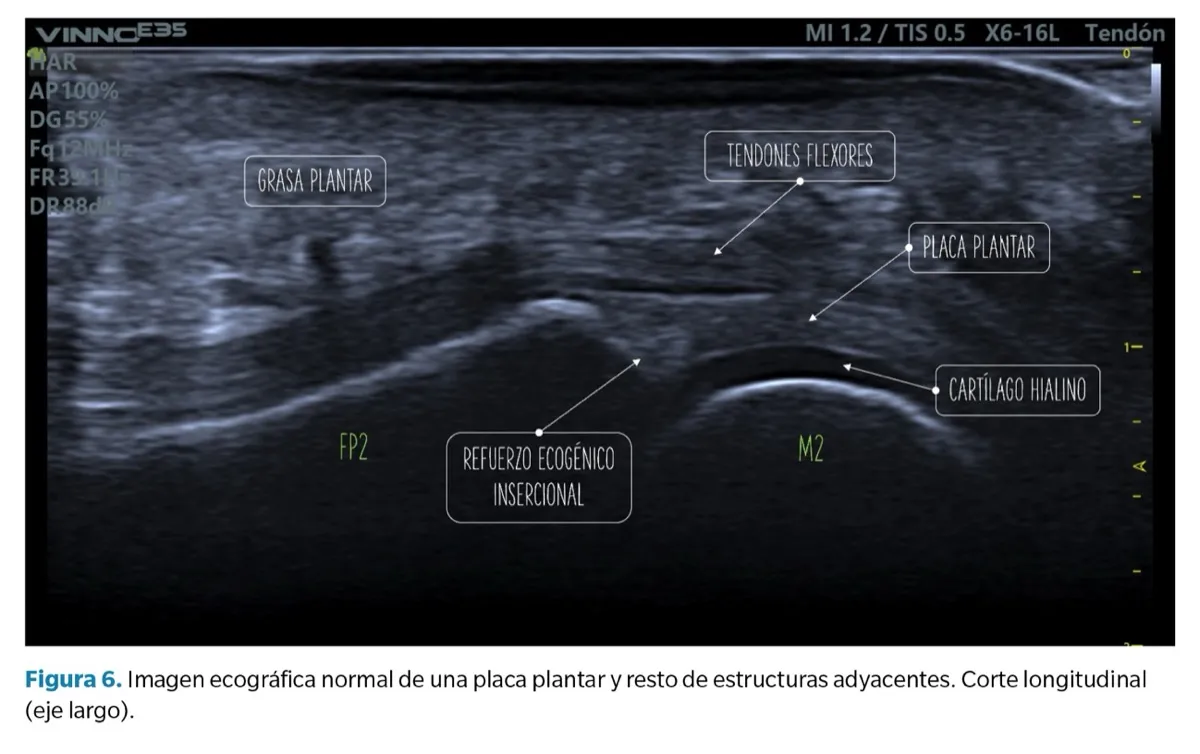

Visión de la placa plantar, de aspecto cóncavo y en continuidad con el cartílago de la falange proximal. Imagen: Revista Española de Podología.

Imagen ecográfica de una placa plantar normal en corte longitudinal. Imagen: Revista Española de Podología.